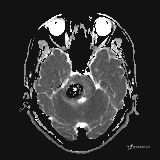

患者男,51岁。

简要病史:患者自述于1周前至某人民医院发现脑干肿瘤(具体不详),为求进一步诊断至我院就诊。

完善颅脑MRI平扫+增强,颅脑CT平扫:

DWI: